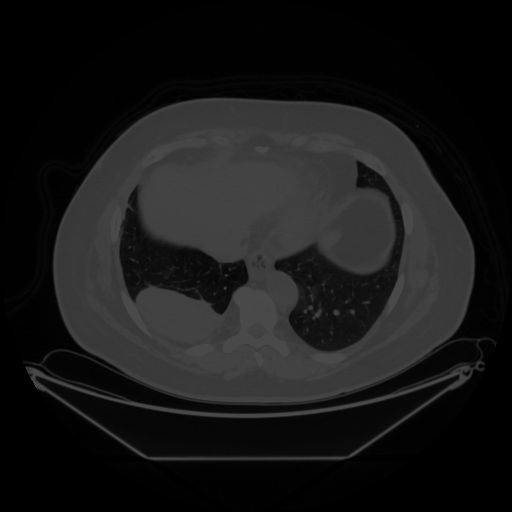

Reconstructed NATIVE CT scan (cycle consistency)

No window - Raw intensity values

Lung window (WL -600, WW 1500 β†’ Low βˆ’1350, High +150)

Mediastinum window (WL 40, WW 400 β†’ Low βˆ’160, High +240)